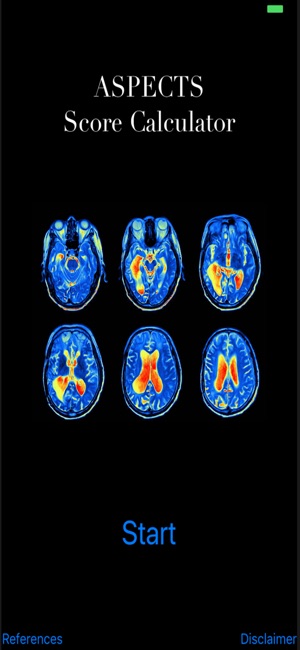

看更多 »ASPECTS Score Calculator

An application for healthcare providers to help calculate an ASPECTS score when you need it most!